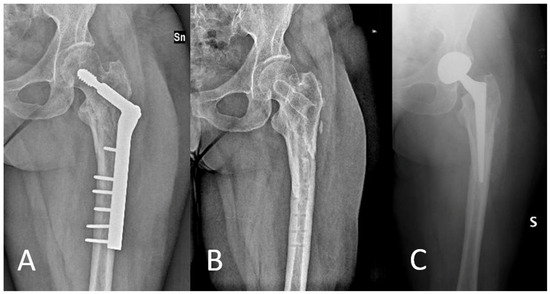

Angle-Adjustable Dynamic Hip Screw Plate for Unstable Trochanteric Fractures in Middle-Aged Patients: Mid-Term Outcomes and Return to Sport

2.1. Surgical Technique